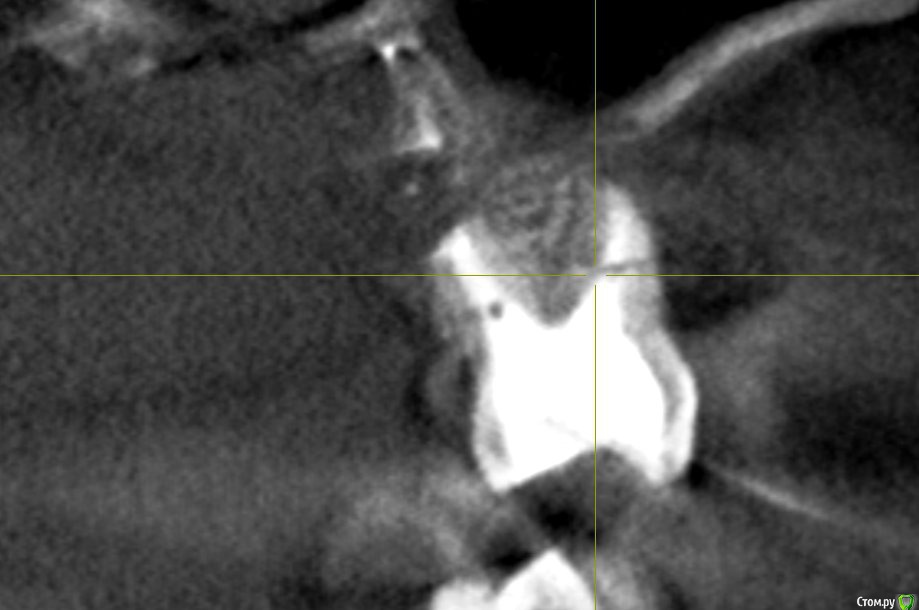

hichin Опубликовано 27 августа, 2019 Поделиться Опубликовано 27 августа, 2019 Здравствуйте, уважаемые стоматологи! Проблемный многострадальный зуб-моляр (26): Дважды попытки удаления кисты левой г/п, вторая попытка удачная, а также гайморотомия и септопластика.Неудачное эндодонтическое лечение, далее повторная попытка перелечивания (смена паст, симптоматика не уходила), которая закончилась сменой стоматолога и лечением с микроскопом. После пломбировки каналов снизилась симптоматика, но пазуха все равно реагировала небольшим утолщением слизистой + любая простуда давала сильную боль на пазуху + зуб. Врачи клиники советовали сделать резекцию. Лоры говорили, что проблема не с их стороны. В члх сделали резекцию с обратной пломбировкой.P.s. так долго эпопея с зубом длится, т.к. все специалисты в один голос говорили о том, что удаление зуба и последующая установка имплантата не факт, что избавит от проблем и будет вообще возможна.Симптоматика c резекцией не ушла.Срезы из свежего КТ прикрепляю. Если можно, прокомментируйте, пожалуйста, срезы. Ссылка на комментарий

hichin Опубликовано 28 августа, 2019 Автор Поделиться Опубликовано 28 августа, 2019 Здравствуйте! По этим срезам изменения а пазухе не значительные,в пределах нормы,характерные для хронического процесса,наличие или отсутствие моляра на него никак не скажется,это самостоятельное заболевание. Над моляром достаточно по..работали,в перспективе он удаляется и замещается на имплант Благодарю вас за ответ.А как быть с оставшимся фрагментом небного корня (если я правильно понимаю, врач удалил не верхушку корня, а как бы середину корня). Реально ли его извлечь и как (через лунку удаленного зуба, через пазуху, тем же путем, что не дошел врач члх)? Основная симптоматика как раз с небной стороны у меня. Ссылка на комментарий